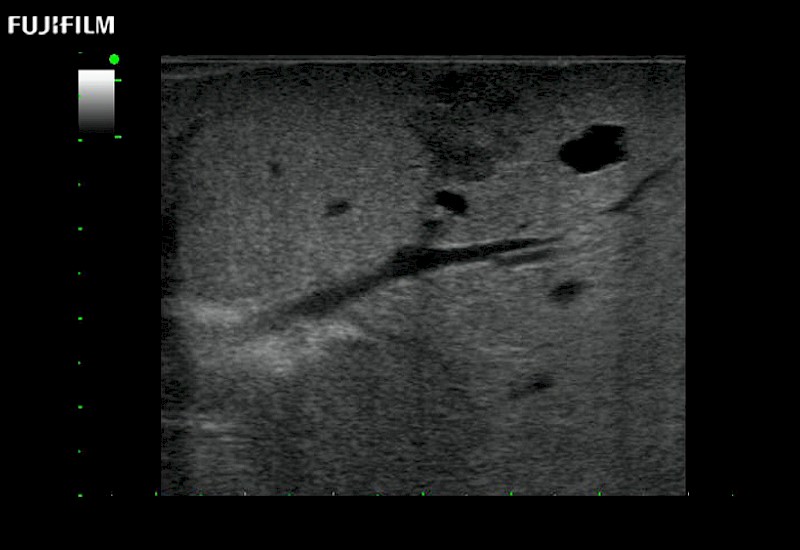

Extraordinary high-resolution digital imaging

for use during open and laparoscopic procedures: Tumor localization & staging, Ablation, Resection, Biopsy, Transplant, Abdominal exploration, Robotic surgery

- Instant feedback on tumor margin delineation

- Valuable information to guide tumor resections

- Instant feedback on tumor margin delineation

- Preferred transducer for liver RFA and biopsies

- Instant feedback on tumor margin delineation

- Instant feedback on tumor margin delineation

- Valuable information to guide tumor resections

- Instant feedback on tumor margin delineation

- Valuable information to guide tumor resections

- Instant feedback on tumor margin delineation

Fujifilm Healthcare continues to listen to the experts, our neurosurgeons, by developing an ultrasound system specifically designed for the Operating Room.

Guidance is the fundamental purpose for all of our surgical ultrasound technology. Fujifilm Healthcare is committed to designing tools that help neurosurgeons navigate inside the human body and provide the necessary information to immediately make critical surgical decisions.

With the ARIETTA Precision the next level of surgical ultrasound is here.